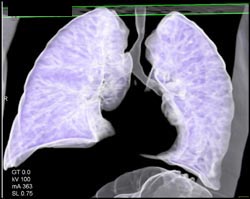

Airway Narrowing Due to Double Arch